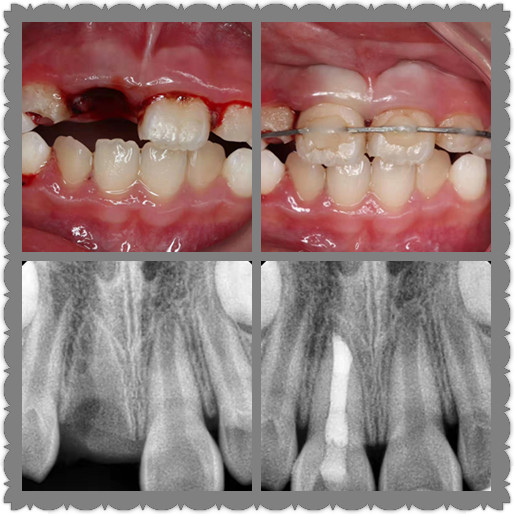

牙齒意外脫落怎么辦?

如果是恒牙,可以嘗試將其放回牙窩,但千萬不要強(qiáng)行放回。如果是乳牙,則不可將其放回牙窩,因?yàn)榭赡軗p害其下方要萌出的恒牙。

需要強(qiáng)調(diào)時(shí)間對(duì)牙齒復(fù)位很重要,越早復(fù)位越可能成功,30分鐘內(nèi)復(fù)位的可能性很大,超過2小時(shí)牙齒則很難復(fù)位。

注意手只接觸牙冠部分(平�?吹靡姷牟糠郑�,不要接觸牙根部分(平常被牙齦和骨頭包繞,我們看不見的部分)。